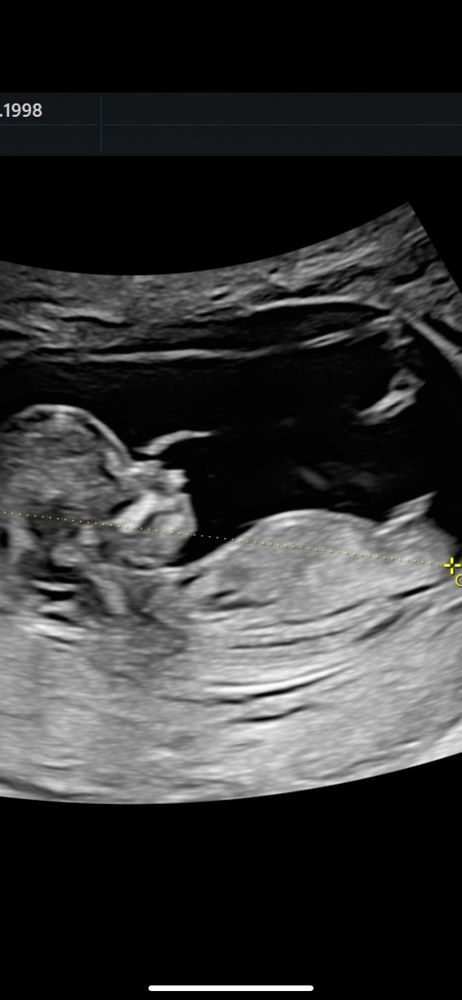

Первый скрининг

Всем привет! Моя первая запись тут.

31 декабря ходили на первый скрининг, платно. Сделали много фото и даже прислали видео, в том числе в 3д, я в шоке коне